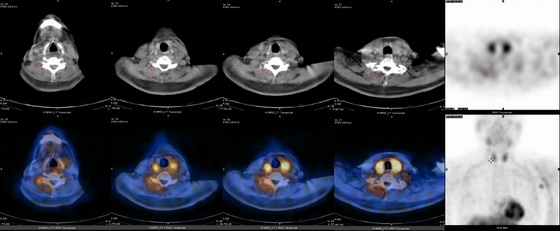

d-spect怎么检查【科普周刊245期】“歪脖子病”怎么办,核医学99mTc-MIBI SPECT/CT检查来助力_https://www.jmylbn.com_新闻资讯_第4张您的检查结果出来了, 99mTc-MIBI SPECT/CT局部肌张力显像检查提示:右侧肩胛提肌、头半棘肌、颈棘肌与多裂肌放射性分布轻度增高。您可以拿着这份报告去找临床医生在检查出来的相应部位注射肉毒素了。